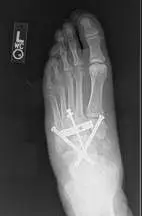

Below are images of Charcot deformity in the midfoot and reconstructive surgery involving an external fixator, which is the metallic structure that you see outside of the area of the foot and leg with pins inserted into the foot and leg to allow support and reduction of the deformity to allow healing.

The lower images are after the removal of the external fixator apparatus, allowing clear visibility of the reconstruction of the midfoot, involving internal fixation with screws and a surgical plate. Notice the reduction of the previous displaced midfoot bones and a recreation of the midfoot arch.